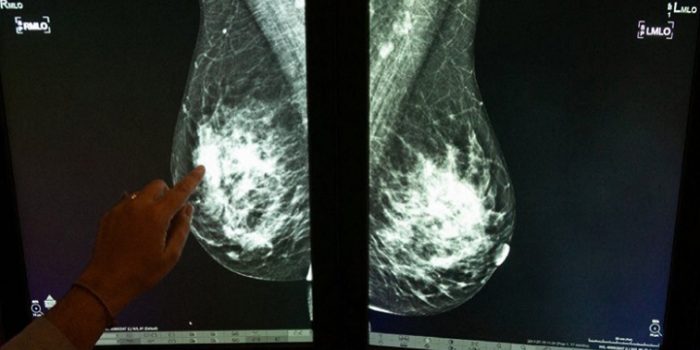

For breast cancer, the tumours can be classified into types:

Ductal carcinoma in situ (DCIS): Non-invasive cancer (meaning it has not invaded the underlying tissue beneath the epithelial cells, and abnormal cells are confined only to the milk ducts.

Invasive ductal carcinoma (IDC): The most common type, where cancer cells break through the duct walls (the cells lining the ducts become cancerous) and invade surrounding breast tissue.

Invasive lobular carcinoma (ILC): Begins in the milk-producing lobules and invades nearby tissue. (The lobules are the part of the breast which produce milk. They are anatomically different from the ducts, which transport the milk to the nipples.)